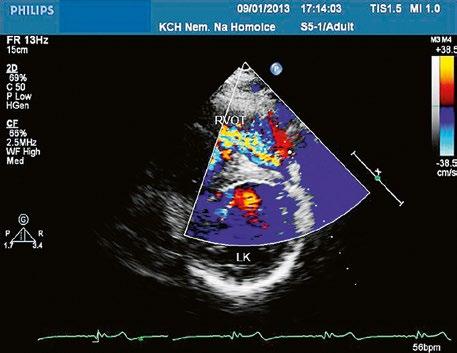

Echokardiografie a jícnová echokardiografie (TEE) je hlavní diagnostickou metodou se zhodnocením morfologie chlopně (Obr. 45.36, Obr. 45.37, Obr. 45.38, Obr. 45.39, Video 45.38), pravé komory (Obr. 45.44) i gradientu (Obr. 45.45). Samotný gradient může být při nevhodném úhlu podhodnocen a je třeba ho korelovat s gradientem na trikuspidální regurgitaci. V dospělosti může mít i významná PS nižší gradient při dysfunkční

Obr. 45.36 Valvární pulmonální stenóza, doming cípů, jemné cípy, srůst komisur (TEE, longitudinální projekce) AP – kmen plicnice, PK – pravá komora, PS – pravá síň